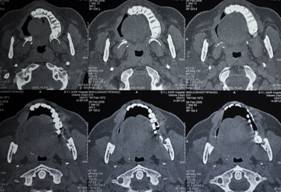

C T SCAN AXIAL SECTION SHOWS EXTENT OF DISEASE

C T SCAN CORONAL AND AXIAL SECTION SHOWS EXTENT OF DEFECT AFTER RESECTION